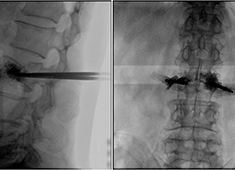

C臂機(jī)在打骨水泥時(shí)是怎么使用的(PKP手術(shù)記錄)

在打骨水泥時(shí)通常要借助C臂機(jī)來進(jìn)行,具體是如何使用的呢?下面通過南京醫(yī)科大學(xué)第二附屬醫(yī)院的一則手術(shù)案例來深入學(xué)習(xí)。首先將患者處于俯臥位,然后利用普愛大平板C臂機(jī)擺位靈活的特點(diǎn),快速定位椎弓根位置...